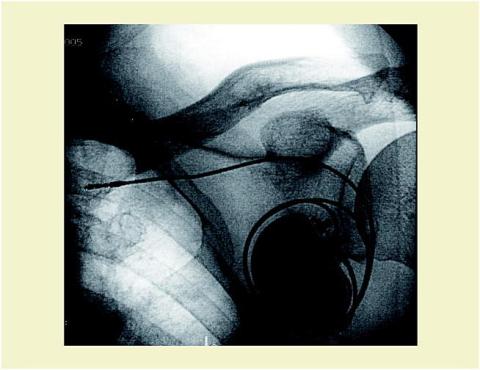

En 87-årig mand fik pga. tredjegrads atrioventrikulært blok implanteret en pacemaker med screw-in-elektrode i højre ventrikel. Pacemakeren var umiddelbart velfungerende, men fjorten dage efter blev patienten indlagt med elektrokardiografiske tegn på pacesvigt og en fornemmelse af hikke. Billedet viser pacemakeren i gennemlysning. Elektroden ses rullet omkring pacemakeren med spidsen beliggende i venstre vena subclavia. Elektroden blev genplaceret, og pacemakeren blev anbragt i stabil position under huden, men allerede næste morgen var elektroden rullet omkring pacemakeren igen. Pacemakeren blev nu sutureret grundigt til den underliggende muskulatur, hvorefter den har fungeret stabilt.

Fænomenet kaldes Twiddlers syndrom. Tilstanden kan i sjældne tilfælde opstå, når der manipuleres med pacemakeren i perioden efter implantationen [1]. Elektroden har ikke kontakt med myokardiet, hvorfor der opstår pacesvigt. Patientens »hikke« skyldes, at pacemakeren stimulerer nervus phrenicus på venstre side.

Det er vigtigt, at placeringen af pacemakeren ikke indbyder til unødig manipulation. Muligheden for fiksering af elektrode og pacemaker bør overvejes hos ældre personer og patienter med meget løs subcutis.